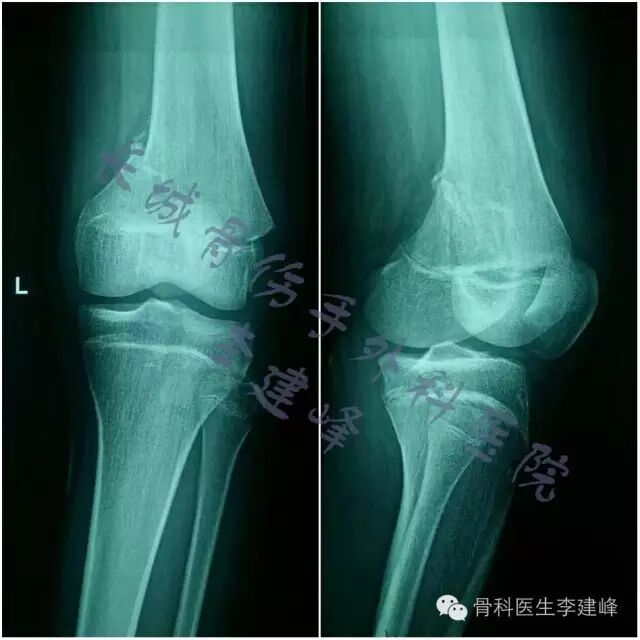

one case:

术前